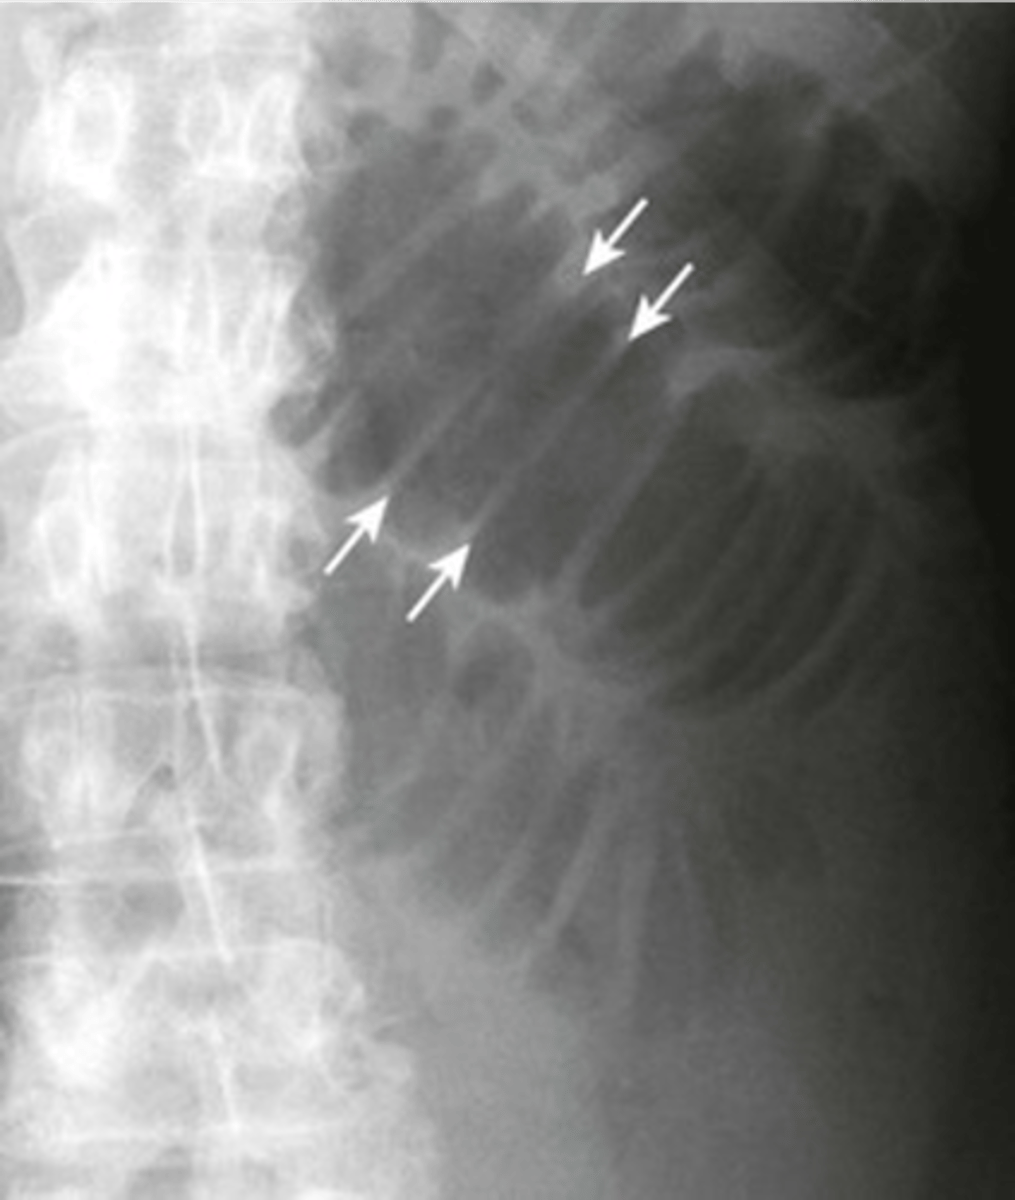

Small bowel enlargement (Valvulae conniventes)

Small bowel (Valvulae conniventes)